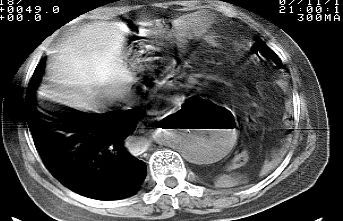

标题: CT10753:女, 64岁 隔疝 [打印本页]

标题: CT10753:女, 64岁 隔疝

女, 64岁 三十年前胸部外伤史, 间断胸闷,

典型左侧膈疝,疝出物为胃和大网膜,纵隔右移

同意左侧膈疝,不过,有过外伤史,左肺有受压征象,同时有胸膜增厚。

左侧隔疝(创伤性?),与外伤关系大。